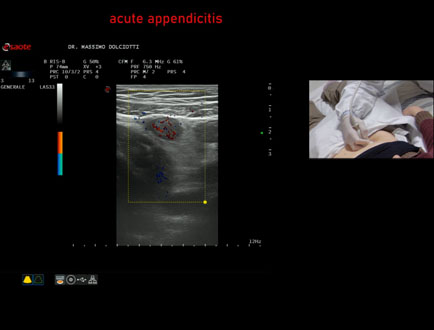

HOME PAGE

Data inserimento: 20/02/2026

Ecografia del: 13/02/2026

Strumento: Esaote MyLab Eight

Sonda: Lineare Multifrequenza 4-15 MHz

Età Paziente: M 22 anni

Motivazione dell'esame: da un giorno dolori addominali in sede ileo-cecale.

Commento all'esame: le immagini ed il video documentano, in sede ileo-cecale, appendice di spessore aumentato (9 - 10 mm - V.N. inferiore a 6 mm) con incremento della vascolarizzazione. Gli elementi ecografici segnalati orientano per appendicite acuta.

Conclusioni: appendicite acuta (acute appendicitis).

In collaborazione: Dr.ssa Marica Manfredi - Ancona, Dr. Ilir Qose - Ancona

Presentazione: Dr. Massimo Dolciotti - Ancona

Elaborazione digitale: Andrea Dini - Ancona